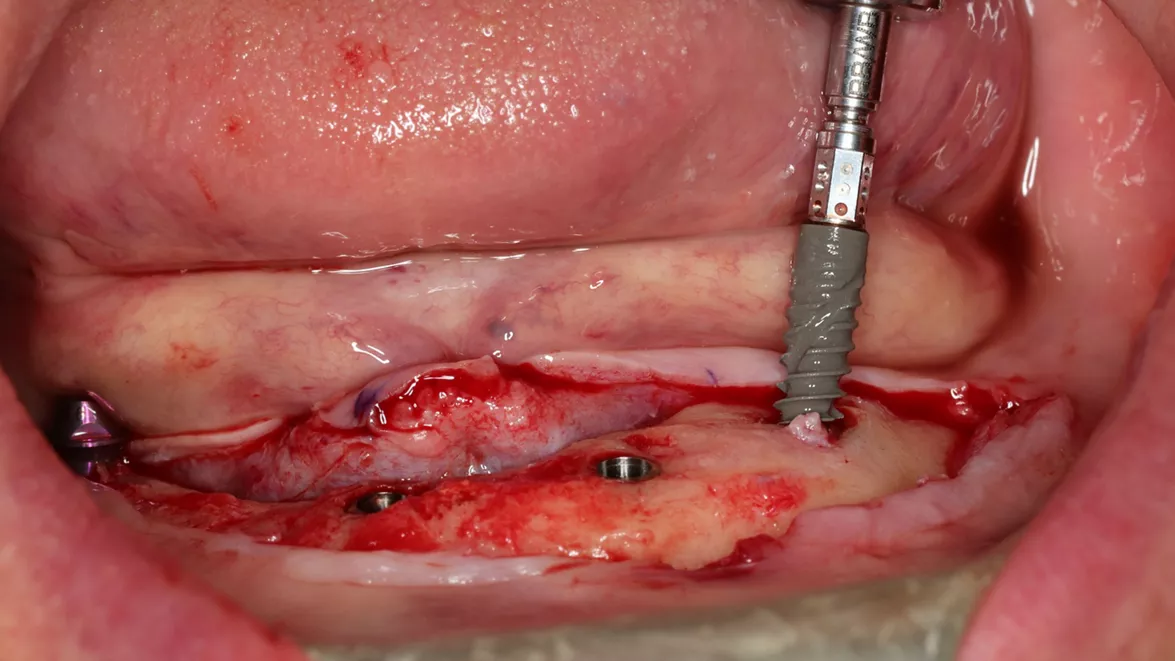

Immediate full-arch rehabilitation with Straumann® Pro Arch BLX (courtesy of J. Caramês)

• Immediate full-arch rehabilitation in the soft bone using Straumann® BLX 3,75 mm from 6 mm till 12 mm in one case (courtesy of B. Sobczak).

• Immediate full-arch rehabilitation using Straumann® BLX 3.75 mm implant in the soft bone (courtesy of L. Cuadrado).

• Immediate full-arch rehabilitation using Straumann® BLX 3.75 mm implant with 10 mm length in the hard bone (courtesy of Dr. L. Swart and P. van Zyl).